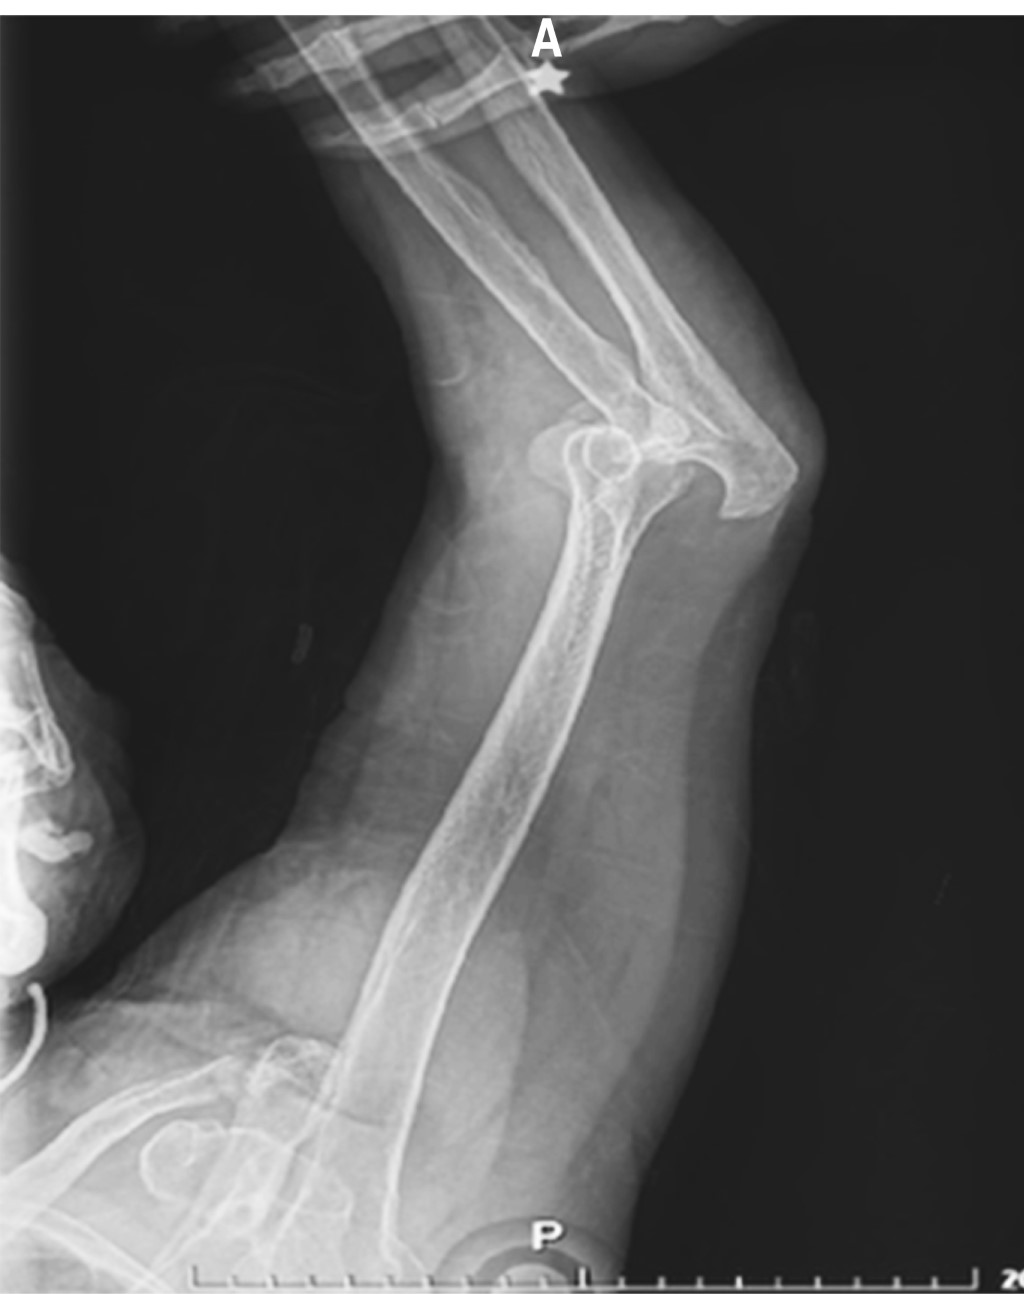

Paciente femenino de 86 años es traída al servicio de urgencias tras caída desde su propio plano de sustentación. El motivo de consulta era dolor en hombro izquierdo y codo ipsilateral. En la exploración física se observaba deformidad en codo y a paciente con miembro torácico por encima de la cabeza, siendo sostenido por extremidad contralateral para disminuir el dolor. La extremidad torácica izquierda se encontraba en abducción máxima y la paciente no era capaz de aducir el hombro. La cabeza humeral era palpable en el borde inferior de la axila. A la exploración neurovascular no se encontraron datos que sugirieran lesión. Radiografías de codo y hombro en proyección anteroposterior y lateral mostraron luxación inferior del hombro (Figuras 1 y 2), así como luxación posterior del codo sin lesión ósea asociada. Ambas lesiones fueron manejadas en quirófano mediante reducción cerrada con paciente bajo sedación. La luxación inferior del hombro fue reducida mediante tracción-contra-tracción del húmero con posterior aducción del hombro. La articulación del codo fue reducida mediante tracción axial con la muñeca en supinación con posterior flexión. Se realizó exploración neurovascular al término donde no se observaron lesiones. Se obtuvieron radiografías de control que evidenciaron correcta localización de la articulación del codo (Figuras 3 y 4) así como de la cabeza humeral (Figura 5). Debido a la mejoría, la paciente fue egresada con férula a 90o e inmovilizador de hombro, iniciando rehabilitación a las 2.5 semanas con movimientos pasivos pendulares de hombro y movimientos de flexión y extensión de codo. El seguimiento se da en la consulta externa a las cuatro semanas, tres y seis meses evolucionando de manera favorable con reincorporación completa a sus actividades de la vida diaria.

Figura 3

Figura 4